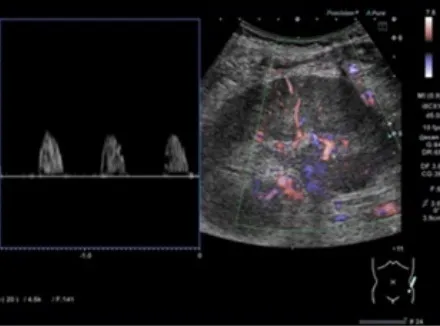

Os achados tomográficos com contraste mostraram um aspecto de "buquê de flores" na fase excretora (Figura 2).

A síndrome de Beckwith-Wiedemann é uma das causas do rim espongiomedular, que se apresenta comachados específicos na tomografia computadorizada, incluindo nefrocalcinose medular, dilatação cística e um padrão de estrias semelhantes a buquês de flores nas papilas renais.